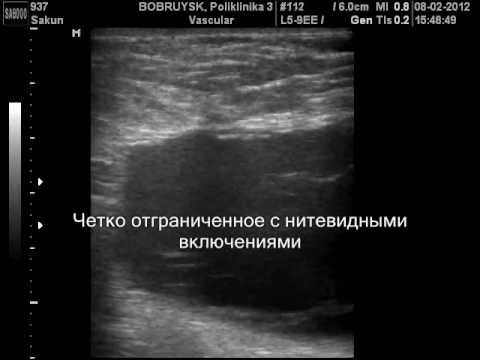

Заподозрить наличие патологии врач может уже при простом визуальном осмотре и пальпации. Для подтверждения диагноза применяются аппаратные способы исследования:

- УЗИ (ультразвуковое исследование). С его помощью можно точно определить размер и местоположение серомы. Применяется для диагностики осложнения на ранних стадиях.